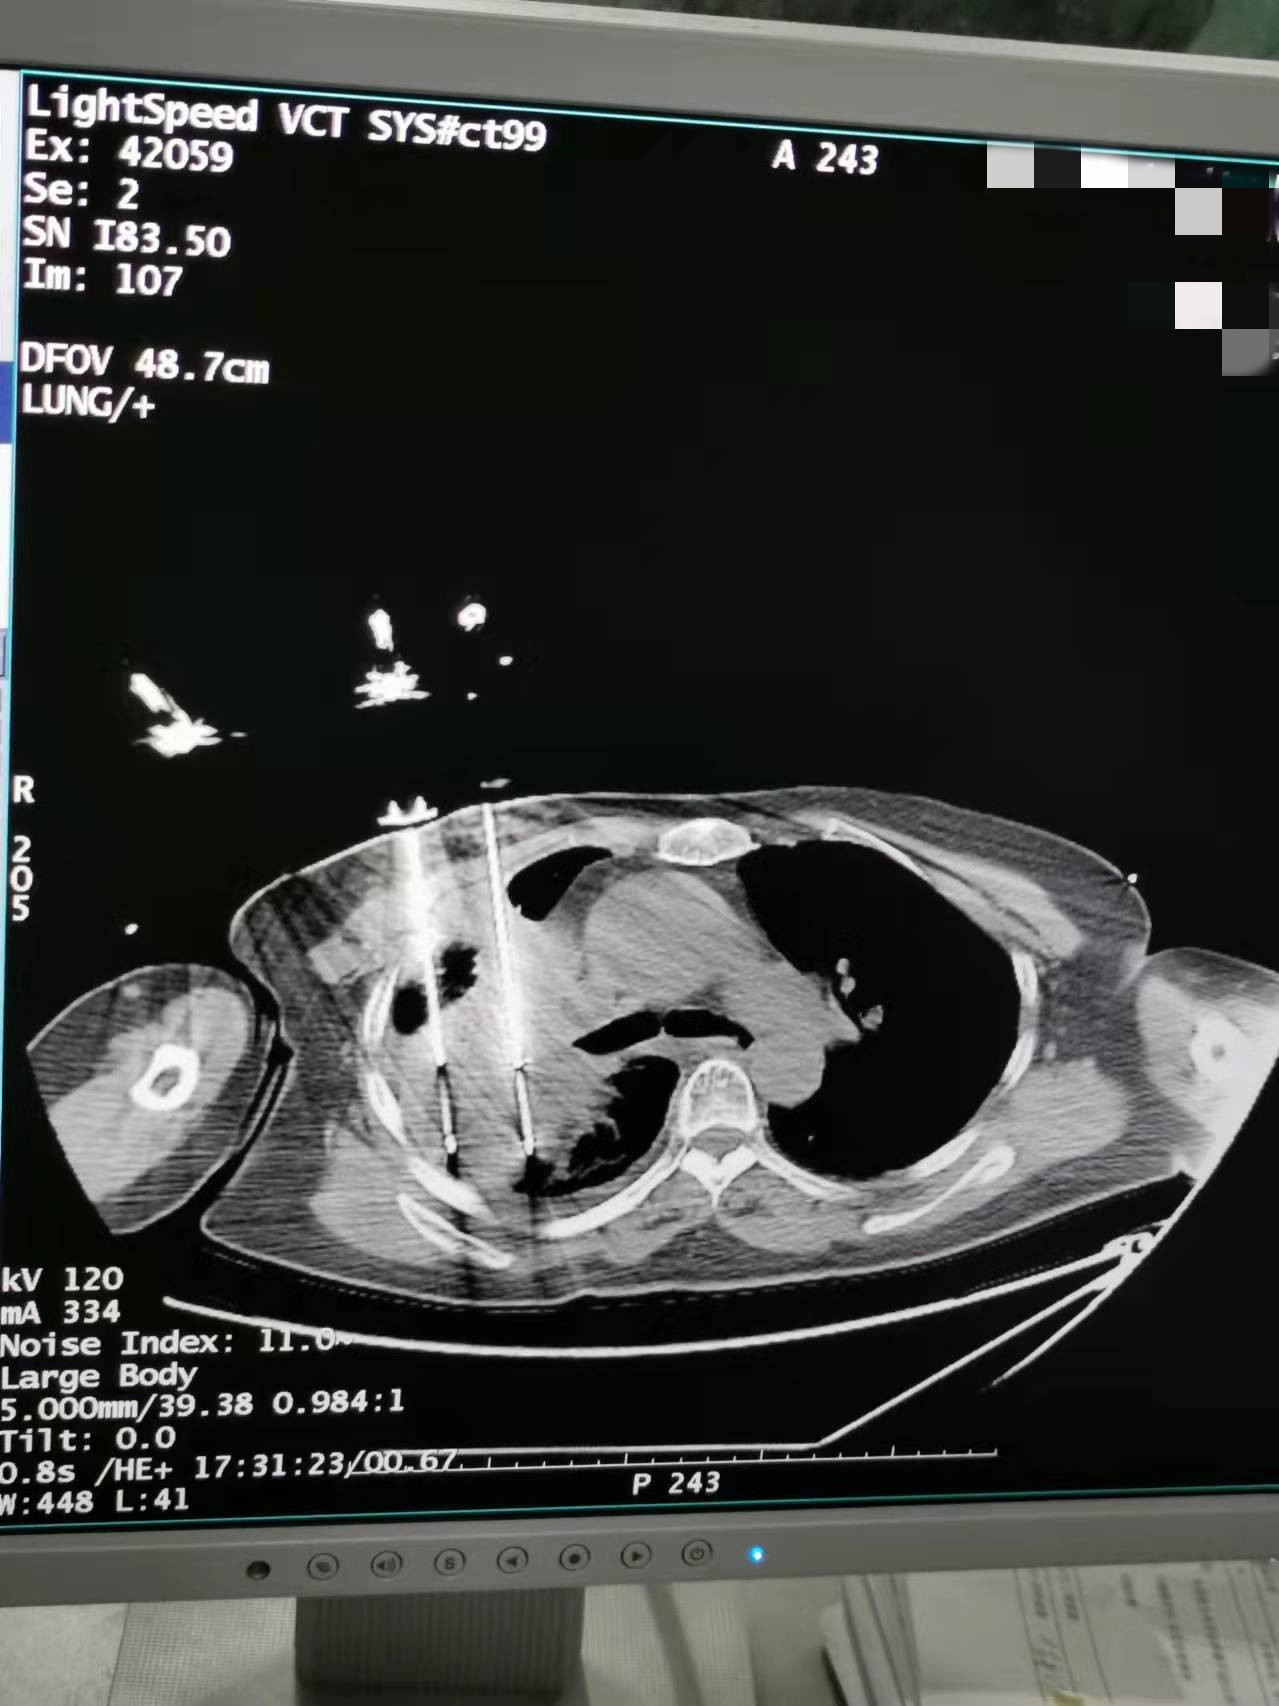

2021年11月份肺部氩氦刀手术

发布人:美国氩氦刀技术官方网站    发布时间:2021/11/26 14:02:23